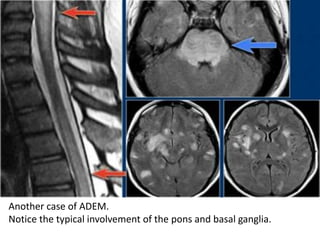

Another case of ADEM.

Notice the typical involvement of the pons and basal ganglia.

On follow up scan almost complete

normalisation.